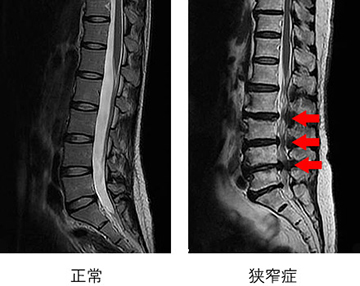

神経の圧迫の程度がわかります。狭窄症では神経の通り道が狭くなります。